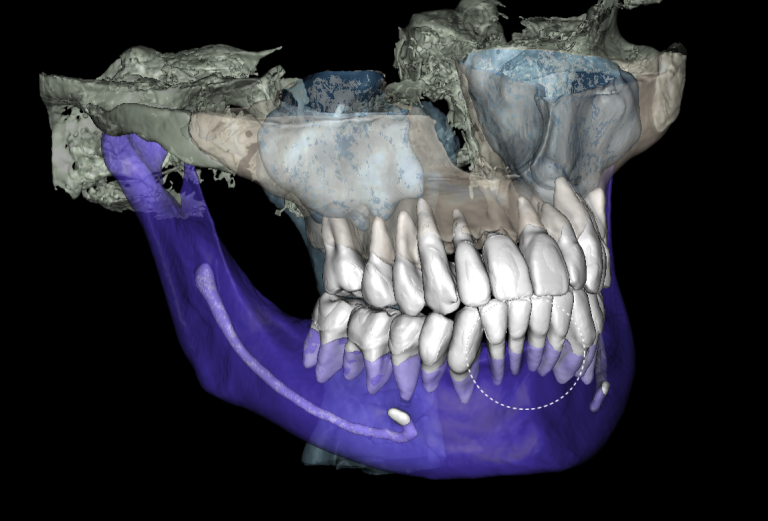

In order to predict the prognosis of the tooth, data from the Diagnocat radiological report and visualization capabilities of the 3D-Viewer tool were utilized, in addition to a clinical examination

Virtual models of the template for guided implant surgery can be created using the “STL” module of Diagnocat. To do this, intraoral scan data is loaded into the module, and a suitable CBCT is selected for merging